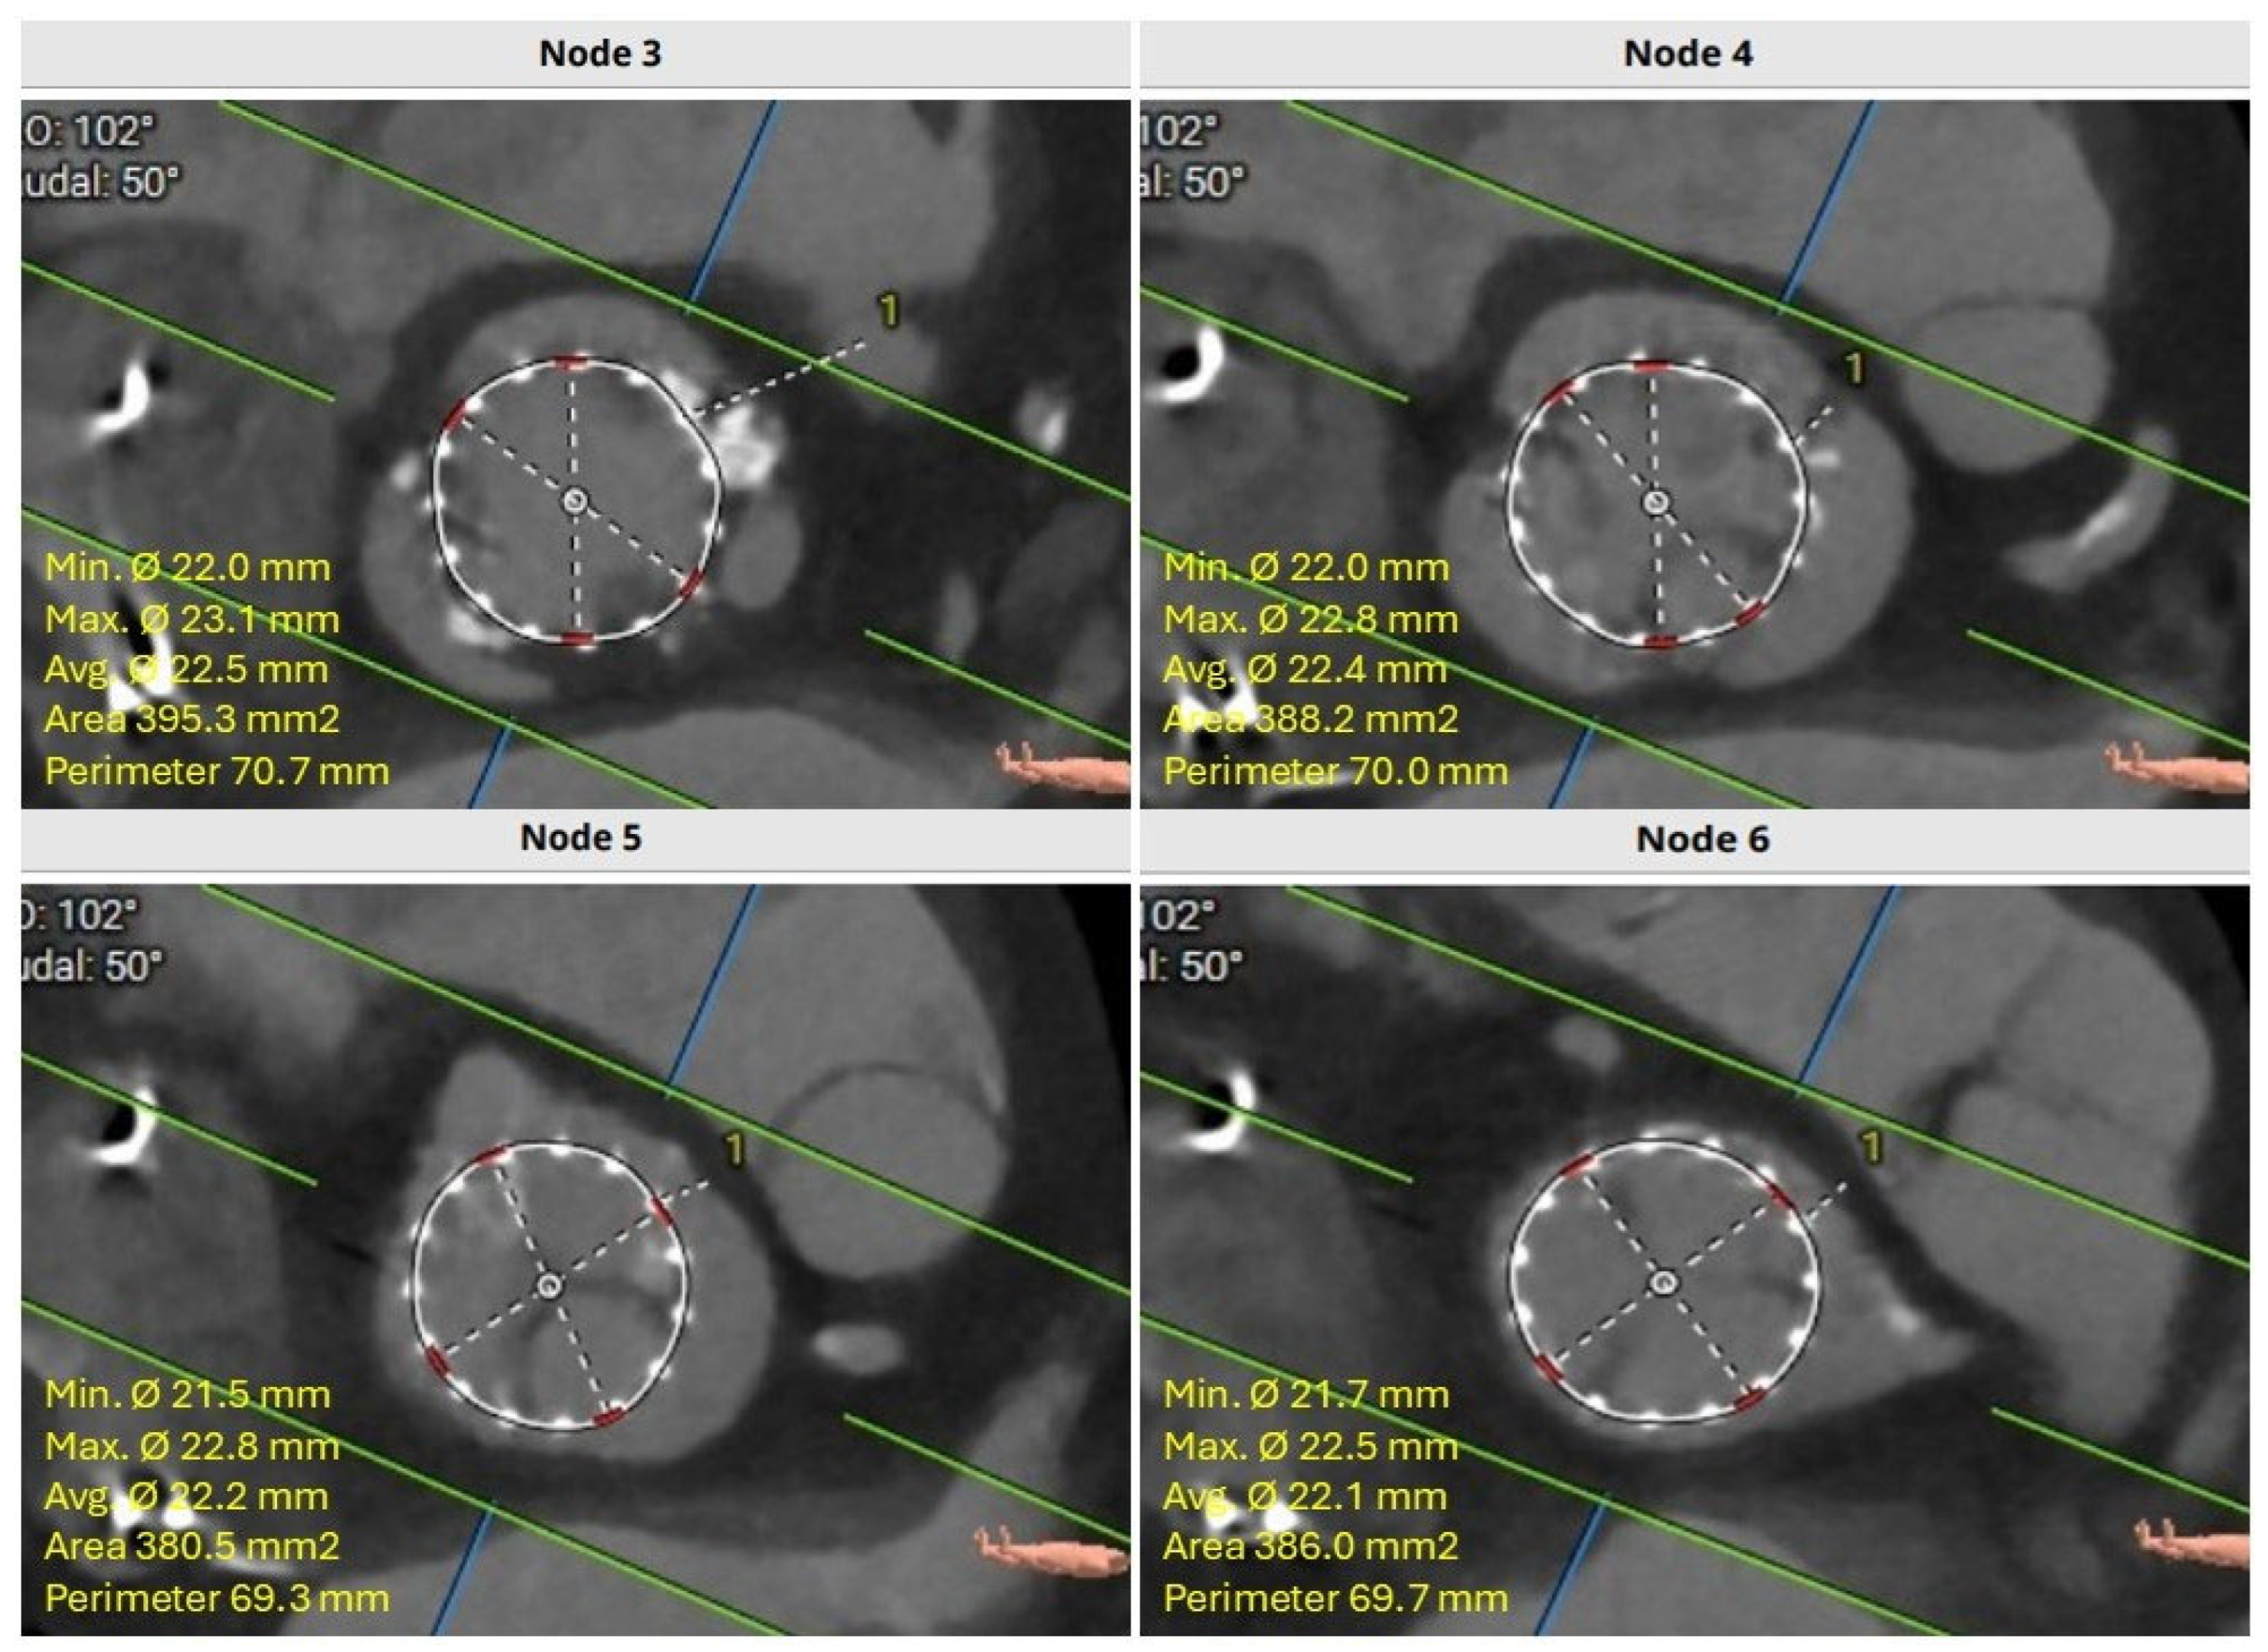

4.3. Neoskirt Plane (NSP)

4.4. Coronary Risk Plane (CRP)